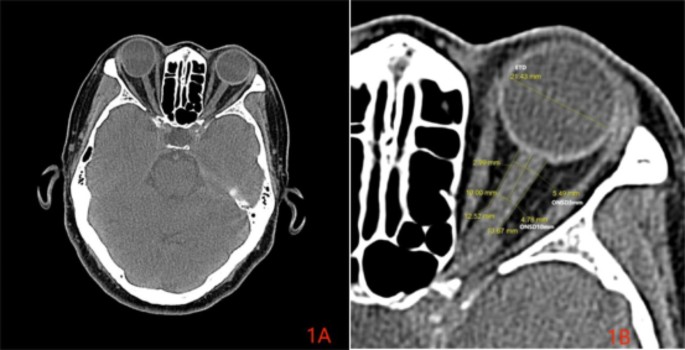

A resident physician and an attending physician with 10 years of experience in radiology department were respectively measured in the brain CT axial images through an electronic caliper. Each person was measured twice and the average value was taken. Then the average value of the measurement results of the two physicians was taken as the final measurement result. In order to ensure the accuracy of measurement, we corrected the magnification of CT images by a unified magnification of 8 times, and the window width and window position were set at 350 and 50 Hu, where the ONSD display was the most clear. ETD and ONSD diameters were measured at the largest dimension. The measurement method is shown in Fig. 1. Additionally, 60 patients were included to measure the ONSD in both axial and sagittal positions, to observe whether there were any differences in ONSD measurements between the two positions. The measurement method is shown in Figs. 2 and 3.